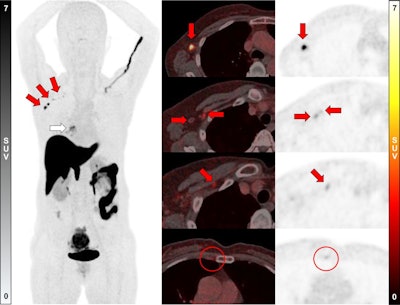

A 58-year-old woman was diagnosed with ER-positive (Allred score 8) ILC in her right breast. Ultrasound and MRI found prominent lymph nodes in right axillary level I area, diagnosed as metastasis on ultrasound-guided fine-needle aspiration. F-18 FES-PET/CT showed a positive mass in right breast (white arrow; SUVmax, 5.6) and multiple F-18 FES–positive lymph nodes in right axillary level I, II, and II/III junction areas (red arrows; SUVmax, up to 12.2). In addition, a small F-18 FES-positive lymph node was observed in the right second internal mammary area (red circles; SUVmax, 1.8). However, biopsy could not be performed because it was too small and not visible on ultrasound; the clinician decided to include internal mammary lymph node in treatment field for adjuvant radiotherapy. The patient underwent lumpectomy with ALN dissection, with five metastases being identified in 13 lymph nodes dissected, and is scheduled to receive adjuvant chemotherapy, radiotherapy, and endocrine therapy.Journal of Nuclear MedicineSemiquantitative analysis revealed a median maximum standardized uptake value (SUVmax) of 3.4 for metastatic ALNs and 1.0 for benign ALNs. With an optimal cutoff of at least 1.2, SUVmax showed a sensitivity of 75% (9/12) and a specificity of 100% (8/8), the researchers reported.